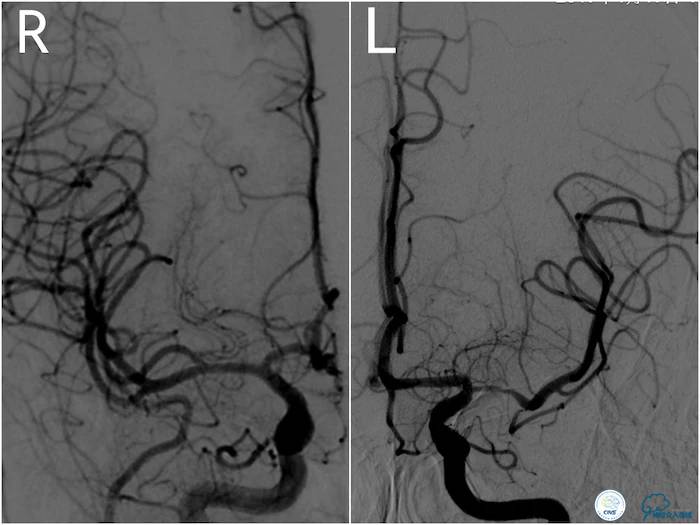

DSA:左大脑中动脉M1段重狭窄,狭窄段较长,大于10mm。同侧大脑前及大脑后动脉对左大脑中动脉供血区域代偿不佳(图8、9)。

图8

图9